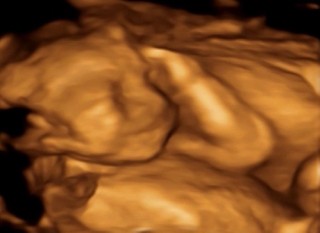

写真:21w3d:さとさん:笑ってる?

4Dエコー外来に行ってきました。画像の中の赤ちゃんの動きと同時に胎動を感じた時すっごく感動しました。写真はニコッと笑ってくれた瞬間でした。

今回は真っ正面でエコーがとれました(*^-^) 笑ってるみたい!最近はポコポコ動いてくれるので元気に育っているようです。